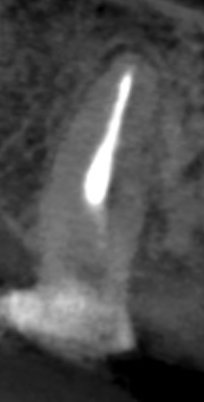

Pre-op

Post-op

臨床にも見事役立つ形成方法のコツであった。